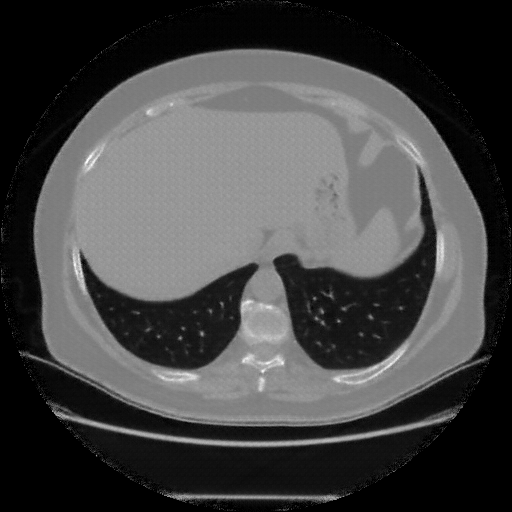

Reconstructed NATIVE CT scan (cycle consistency)

Full window (WL 1023.5, WW 4095 β†’ Low βˆ’1024, High +3071)

Actual HU range: [-1024.0, 993.2]

Lung window (WL -600, WW 1500 β†’ Low βˆ’1350, High +150)

Actual HU range: [-1350.0, 150.0]